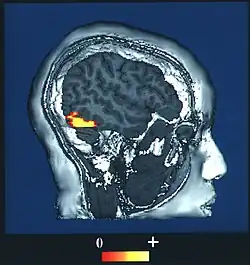

![]() Computer-enhanced fMRI scan of a person who has been asked to look at faces. The image shows increased blood flow in cerebral cortex that recognizes faces (FFA). | |

The fusiform face area (FFA, meaning spindle-shaped face area) is a part of the human visual system (while also activated in people blind from birth[1]) that is specialized for facial recognition.[2] It is located in the inferior temporal cortex (IT), in the fusiform gyrus (Brodmann area 37).

The FFA is located in the ventral stream on the ventral surface of the temporal lobe on the lateral side of the fusiform gyrus. It is lateral to the parahippocampal place area. It displays some lateralization, usually being larger in the right hemisphere.